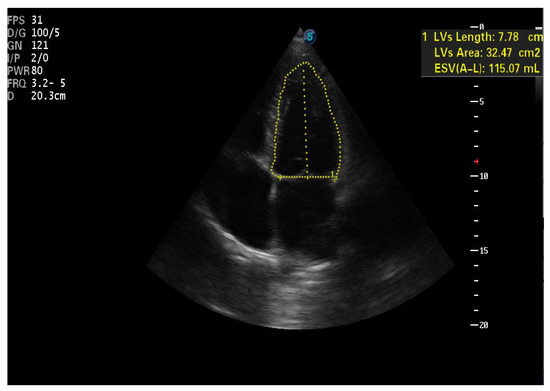

| IVS (cm)—PLAX | 1.93 | 1.27 | 1.2 |

| PLVW (cm)—PLAX | 1.38 | 1.16 | 1.05 |

| RV diameter (cm)—PLAX | 4.1 | 3.7 | 3.59 |

| LVTDV (ml/m2bs)—A4C | 114.5 | 100.7 | 90.8 |

| LVTSV (ml/m2bs)—A4C | 63.8 | 54.07 | 50.9 |

| LVEF (%)—A4C | 43 | 46 | 44 |

| RVTDV (ml/m2bs)—A4C | 33.3 | 50.5 | 22.2 |

| RVTSV (ml/m2bs)—A4C | 15 | 20.6 | 13.5 |

| LATSV (ml/m2bs)—A4C (*) | 38.2 | 44.5 | 37.1 |

| RATDS (ml/m2bs)—A4C (*) | 22.7 | 50 | 10.4 |